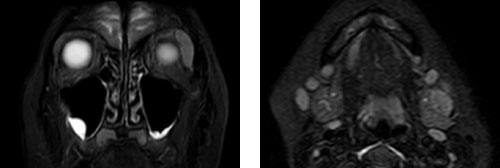

IgG4関連ミクリッツ病では、唾液腺、涙腺、顎下腺、舌下腺などに、両側性、対称性、持続性の腫脹がみられます。 以下に示すIgG4関連ミクリッツ病患者では、両側顎下腺、舌下腺、左側涙腺の腫脹が認められます。

MRI所見においても両側顎下腺ならびに左側涙腺の腫脹が認められます。